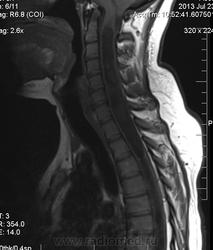

Сирингомиелия шейно-грудной локализации? Аномалия Арнольда-Киари I. Платибазия.

здоровенная сирингогидромиелитическая киста (по видимому, "высокого давления"), мальформация Киари 1.   также имеются признаки внутренней окклюзионной гидроцефалии.

Думаю, да. У человека наверняка сильно болит голова.